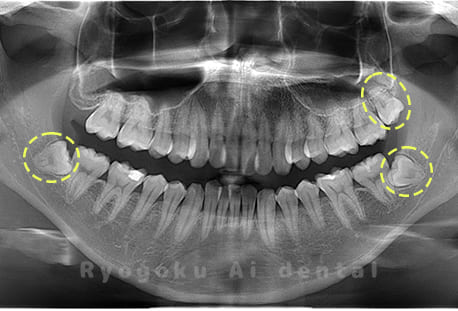

Case03

- 原因

- 上顎、下顎の親知らず

- 治療内容

- 上下4本の親知らずを抜歯したケースです。

<リスク・副作用>

手術後は痛み、腫れ、痺れなどの副作用が生じる場合があります。